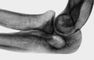

Рентгенологически О. проявляется очагом деструкции различной формы, расположенным в губчатом или компактном веществе кости. Размеры очага от нескольких миллиметров до нескольких сантиметров. Он может иметь четкие или расплывчатые контуры. Нередко прослеживается реакция окружающей костной ткани в виде остеосклероза, а внутри самого очага может определяться тень секвестра. При туберкулезных О. продуктивная реакция костной ткани обычно выражена слабо, в виде неширокой склеротической каймы вокруг деструктивного очага (рис. 1). Для этой формы О. характерно формирование губчатого секвестра (рис. 2). Если воспаление костной ткани развивается в метафизарной области и очаг его расположен эксцентрично, особенно у детей, возможна линейная или слоистая периостальная реакция, свойственная туберкулезному О. Диагноз уточняют с помощью томографии, радионуклидного исследования (см. Радионуклидная диагностика) и биопсии костной ткани. При специфическом О. используют микробиологические и иммунологические методы исследования. Дифференциальный диагноз проводят с остеоид-остеомой, кортикальной лакуной, эозинофильной гранулемой, хондробластомой, ограниченным асептическим некрозом, кистевидными образованиями дегенеративно-дистрофической природы и др.